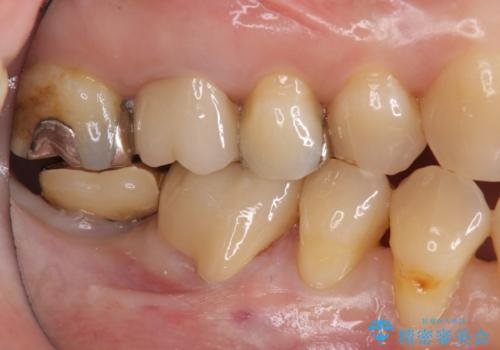

- 右下6 仮歯+セラミッククラウン 11,000円+121,000円費用は治療当時の料金となります

クラウンでは歯のがたつきを修正することもできます。

虫歯の除去と歯の捻転の両方を解決することができました。